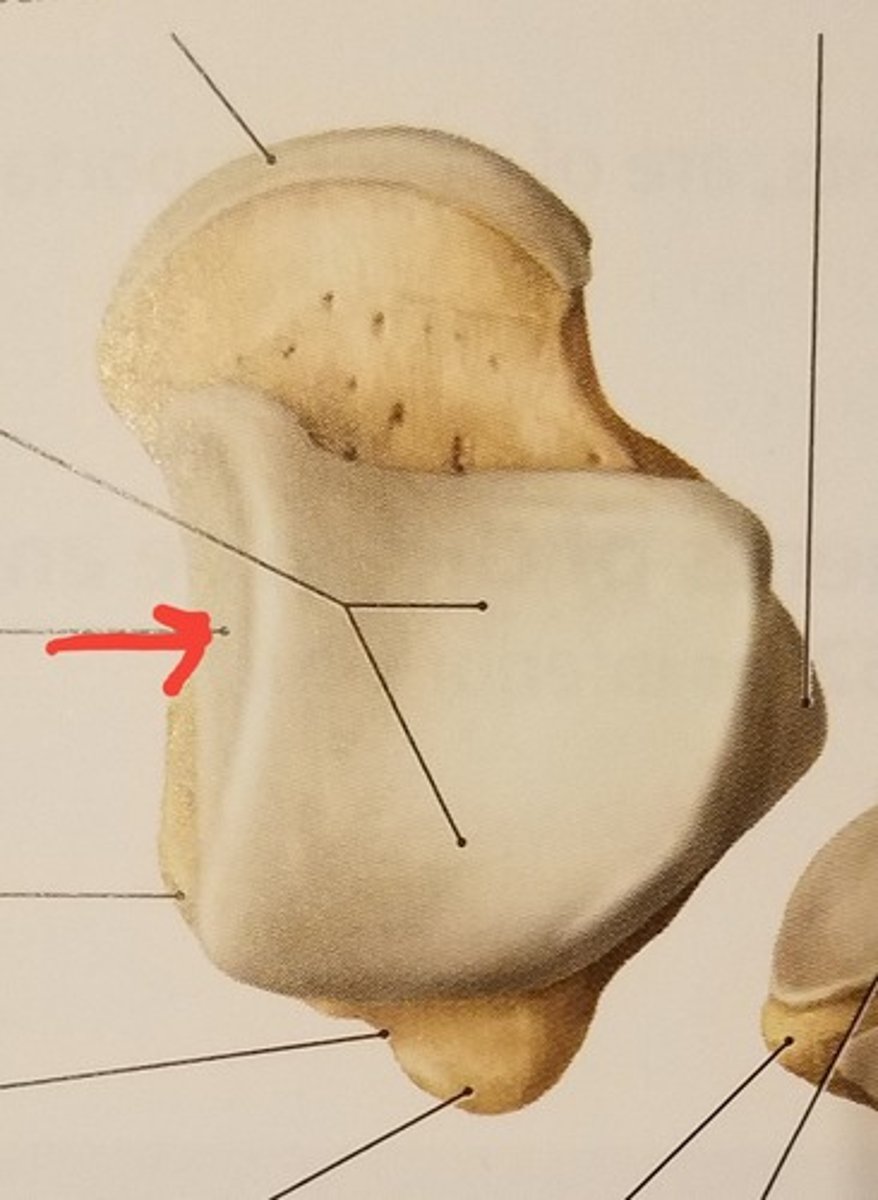

Patella

Apex

inferior surface for patellar ligament

Base

superior surface for quadriceps tendon

Medial articular surface (for medial condyle of femur; smaller)

Lateral articular surface (for lateral condyle of femur; bigger)